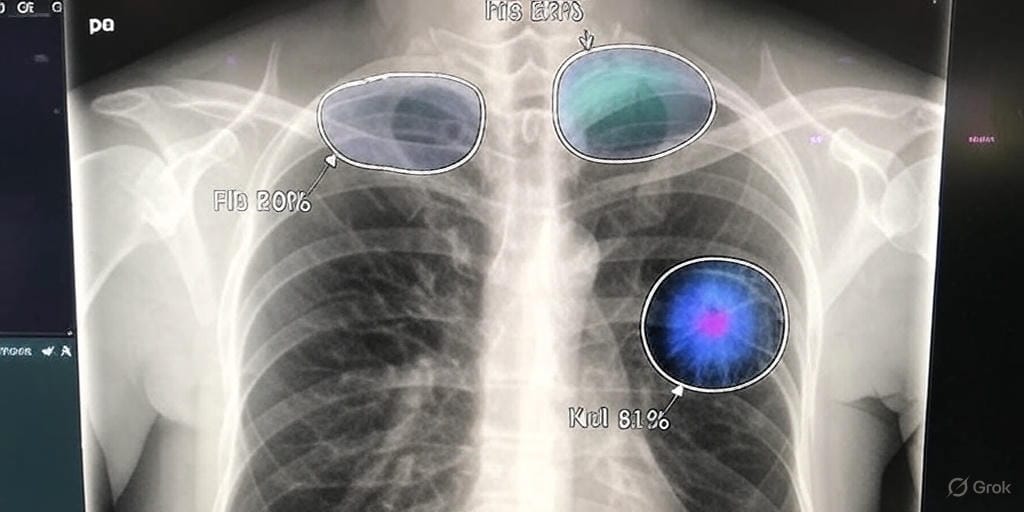

The new AI-powered system leverages advanced machine learning algorithms to analyze a minimal set of X-ray images and generate highly accurate 3D models of bone structures. Unlike conventional CT scans, which require multiple X-ray projections taken from various angles, this technology achieves comparable results with significantly fewer inputs. By training on vast datasets of existing medical imaging records, the AI has learned to interpret subtle patterns in 2D X-rays, extrapolating them into detailed 3D reconstructions. This process not only minimizes radiation exposure but also reduces the time and cost associated with diagnostic imaging.

The system’s ability to function with just two to four X-rays is particularly revolutionary. Traditional CT scans expose patients to higher doses of radiation, which can accumulate over time and pose risks, especially for individuals requiring frequent imaging, such as those with chronic conditions or trauma-related injuries. By contrast, the AI-driven approach uses standard X-ray equipment already available in most medical facilities, making it a scalable solution that doesn’t require expensive new hardware.